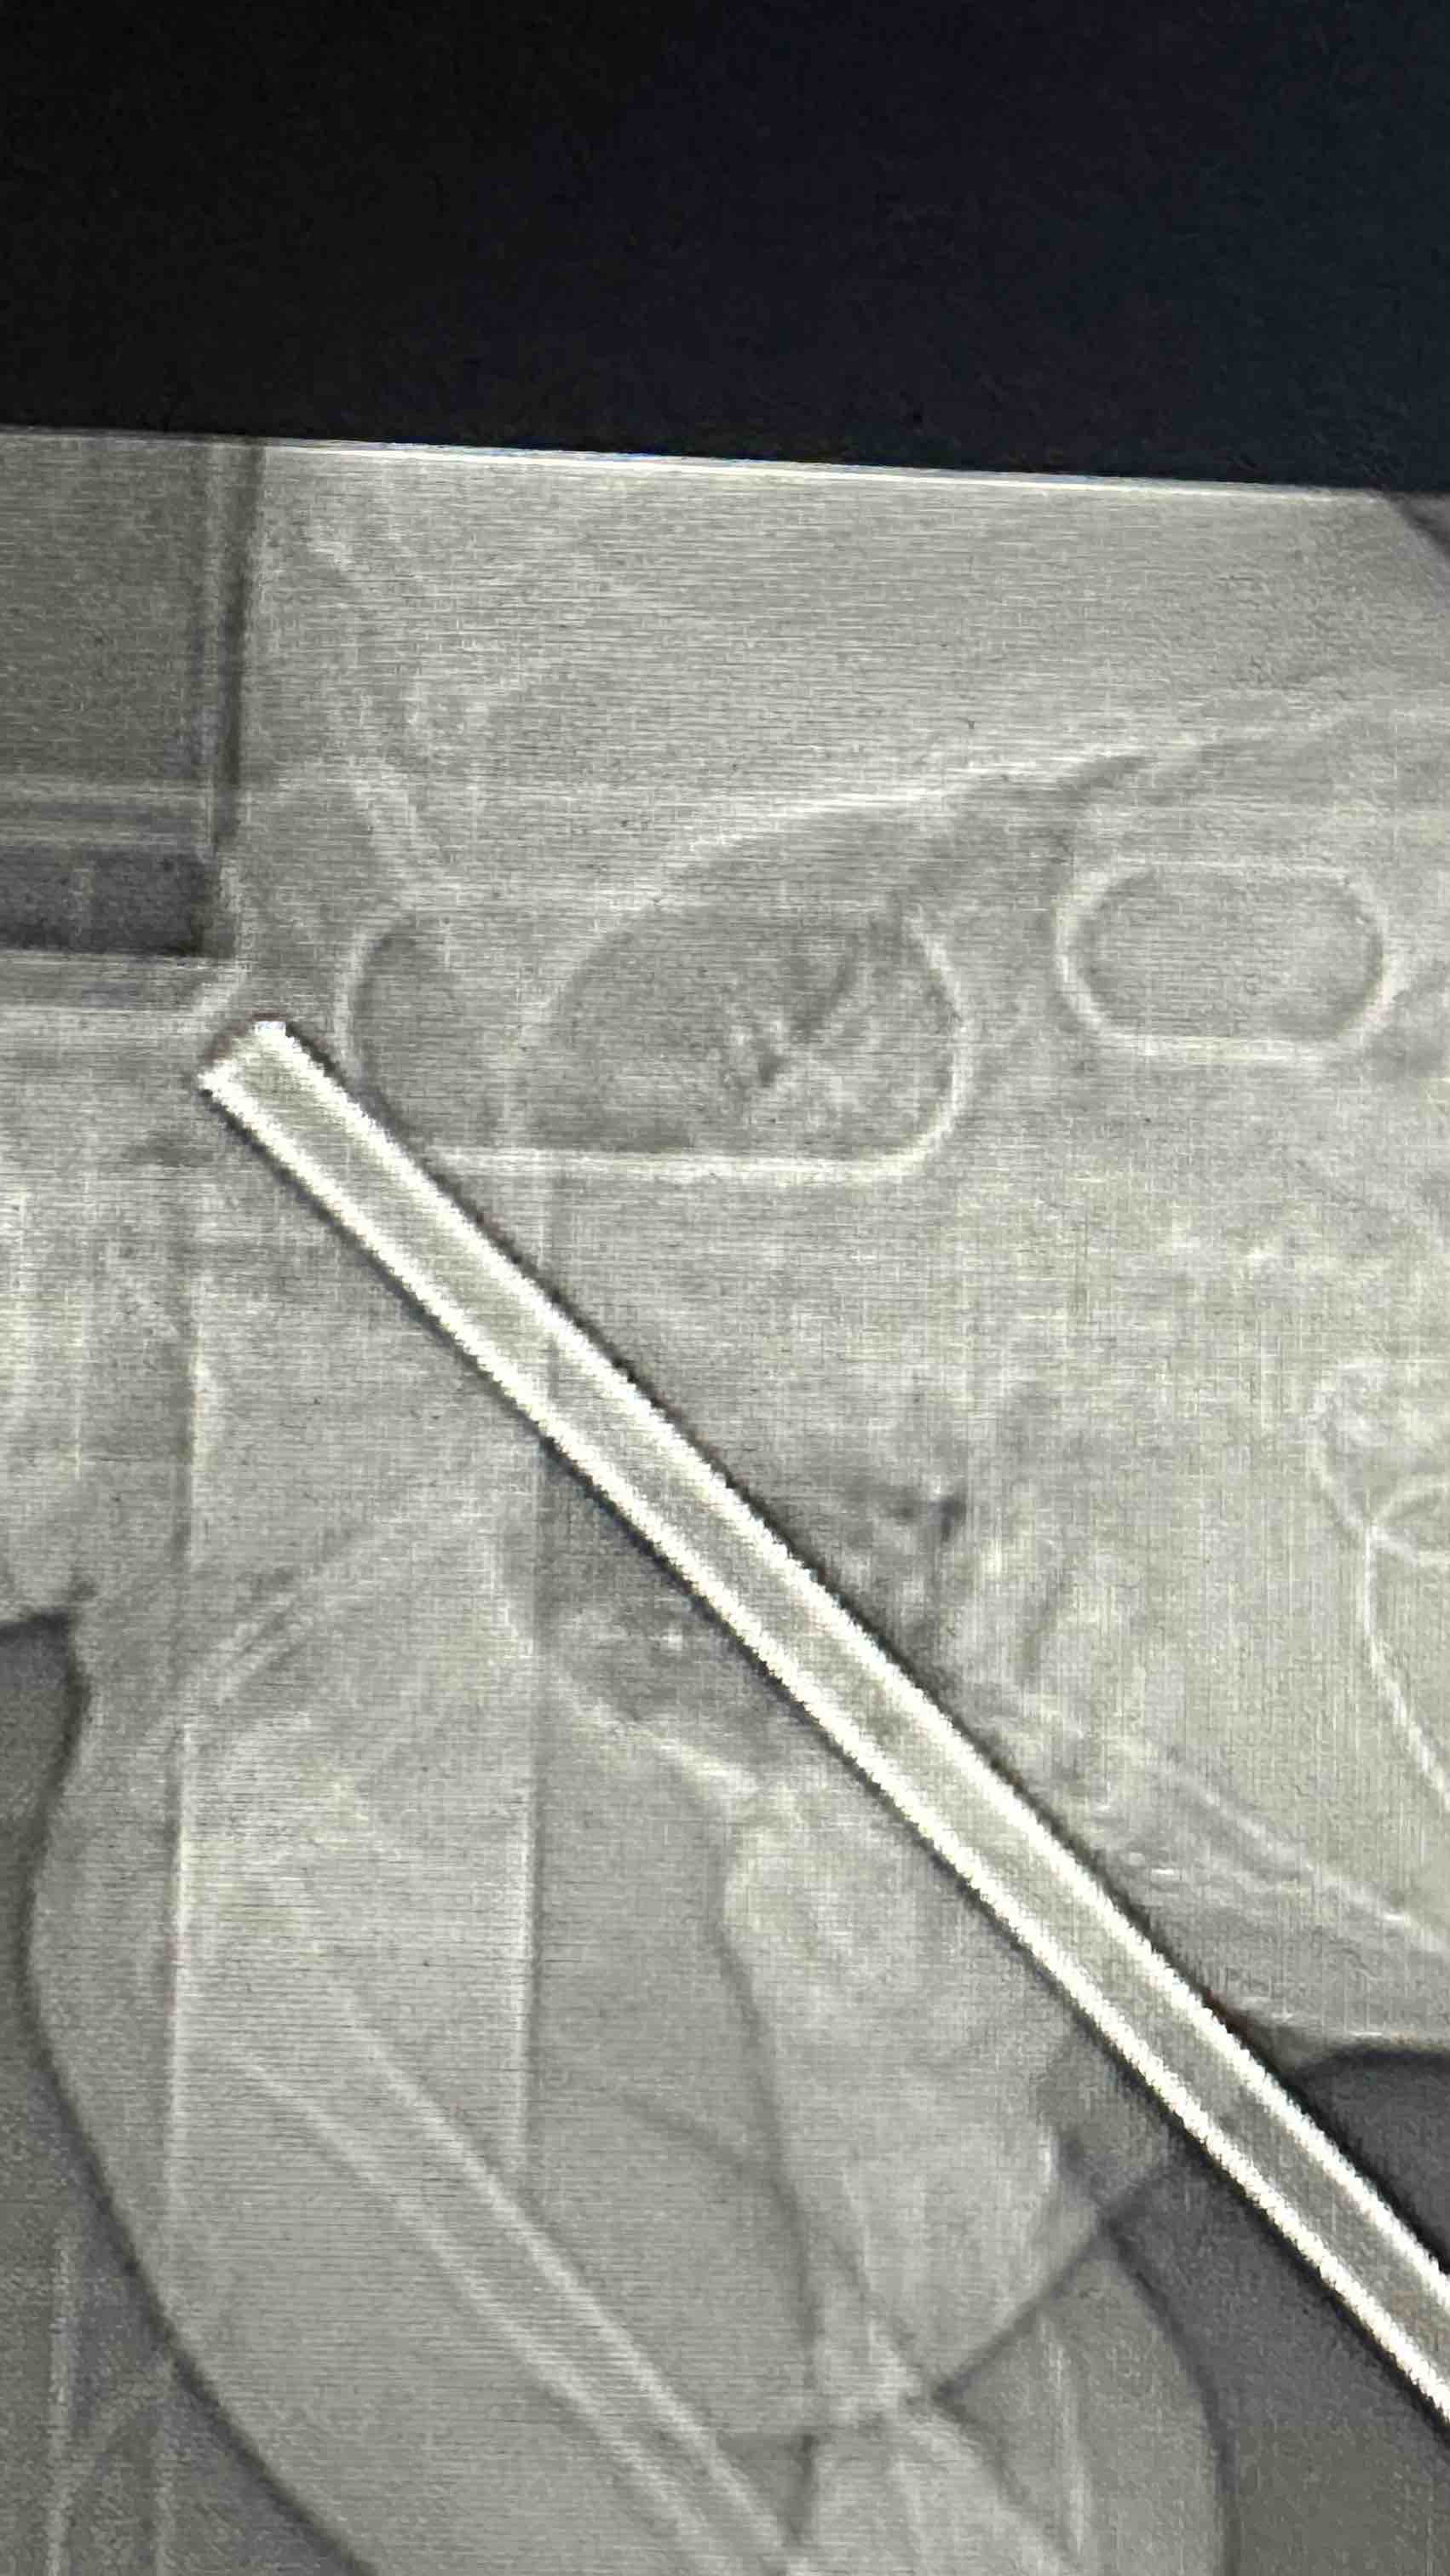

My stepdad, John Davis, of Nashville, IL, suffered a very traumatic accident while working outside near Coulterville. He fell from a ladder onto a pole, which impaled him from his right side under his shoulder and through to the left side of his neck. Emergency responders quickly responded to cut him from the pole to life-flight him to SSM Health Saint Louis University Hospital for emergency trauma surgery.

A team of surgeons worked to remove the pole, repair internal damage, and place a chest tube related to the penetration of the pole through his lung. John is currently in the ICU, where he’s expected to have a long recovery ahead. We are unbelievably grateful he is still with us, but the road ahead is going to be tough — physically, emotionally, and financially.